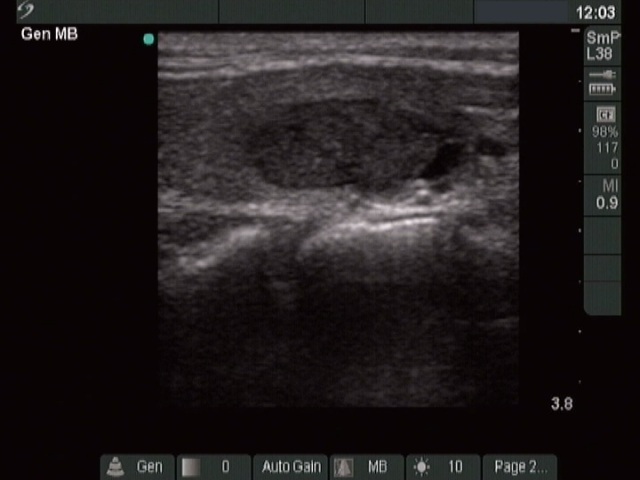

Ethanol sclerotherapy: thyroid cysts - Case 11

Three months after the sclerotherapy (ultrasonographic picture 2)

Left lobe, longitudinal scan.